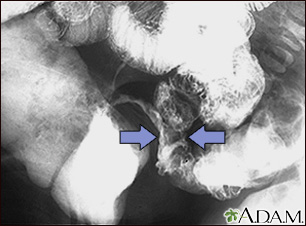

This lower abdominal x-ray shows narrowing (stenosis) of the end of the small intestine (ileum), caused by Crohn disease. Crohn disease typically affects the small intestine, whereas ulcerative colitis typically affects the large intestine. A solution containing a dye (barium), was swallowed by the patient. When it passed into the small intestines, this x-ray was taken (lower GI series).